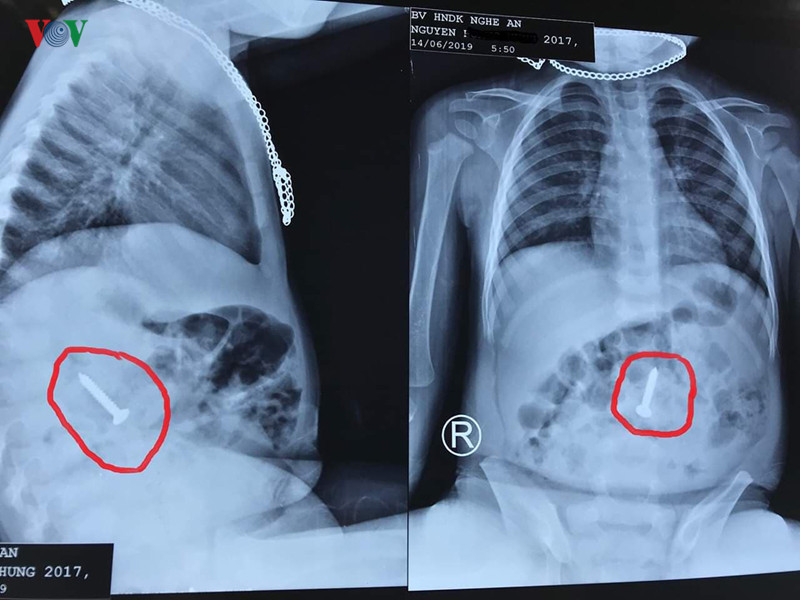

Trước đó, vào ngày 14-6, các bác sỹ tại bệnh viện Hữu nghị đa khoa Nghệ An cũng đã tiếp nhận bệnh nhi N.H.H (20 tháng tuổi). Bé H. được chẩn đoán là đã nuốt phải dị vật kim khí. Kết quả nội soi cho thấy tại đoạn cuối tá tràng của bệnh nhi có hình ảnh dị vật kim loại một đầu sắc nhọn (ốc vít kim loại) dài 3,5 cm.

Chiếc đinh vít trong dạ dày cháu H. (ảnh: Bệnh viện cung cấp)

Sau đó, chiếc đinh vít được các bác sỹ tiến hành gắp ra ngoài. Các bác sĩ cảnh báo trẻ dễ nuốt dị vật kích thước nhỏ. Nếu không được xử lý kịp thời, nó sẽ mắc kẹt ở thực quản, đi vào đường thở, ảnh hưởng tính mạng của nạn nhân.